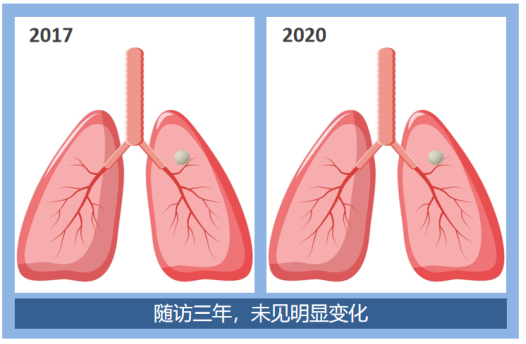

第二组:磨玻璃结节

这是两例磨玻璃结节病例,肺结节既可以在三年的随访中保持不变,也可以在随访7个月后吸收消失了。